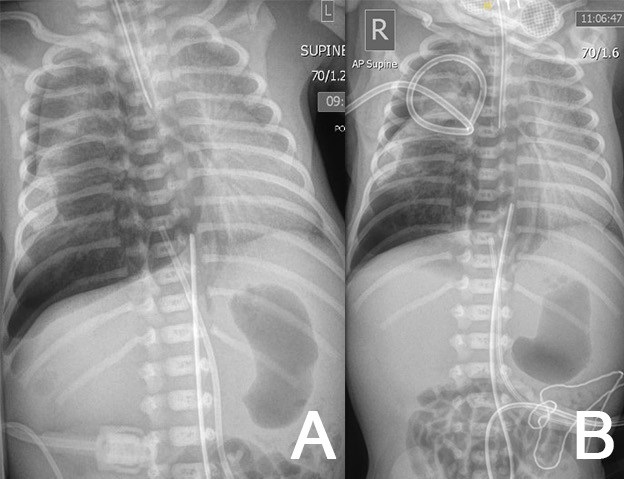

At 3 hours of age, due to sudden loss of chest movements and volumes on ventilation, the neonate was re-intubated. There was ongoing respiratory distress and CXR confirmed a right-sided tension pneumothorax (Fig. 1A). Needle aspiration followed by tube thoracocentesis (TT) with the underwater seal was undertaken (Fig. 1B) . The drain was placed on low-flow suction. One hour later, further desaturation and transillumination indicated a large residual pneumothorax, necessitating a second chest drain, also placed on low-flow suction. Ventilation improved and he remained on 25% FiO2.

Chest and abdominal radiographs showing right-sided pneumothorax (first diagnosis) – before (A) and after (B) drain 1.